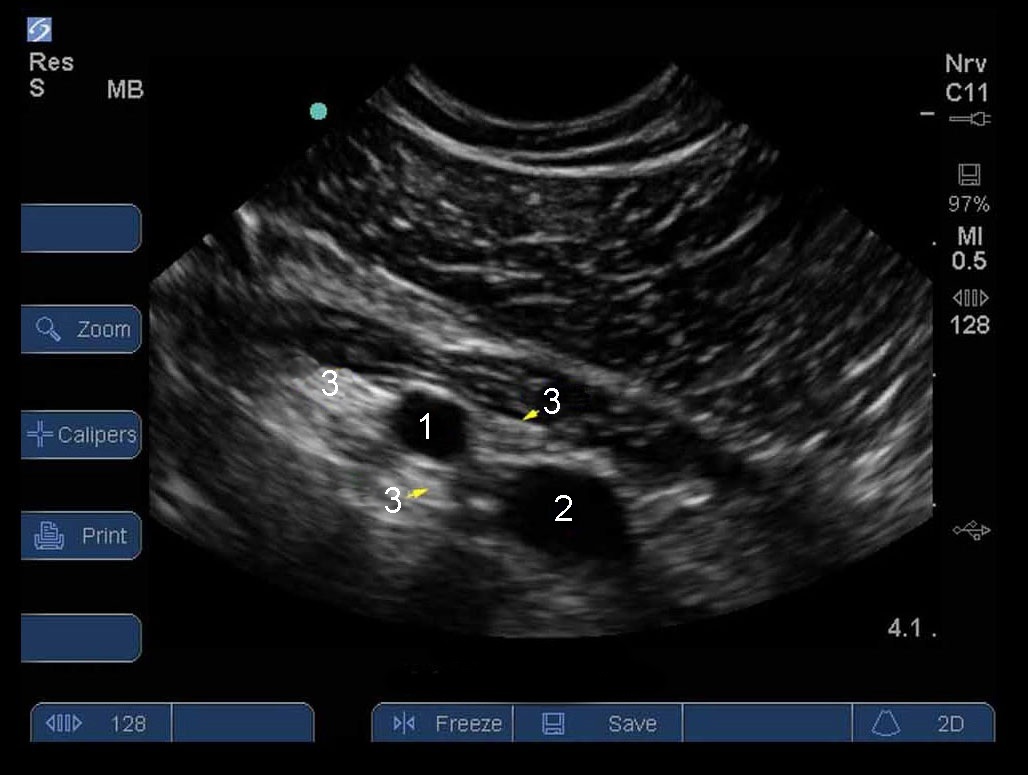

锁骨下臂丛神经 1 级

动脉

静脉

神经